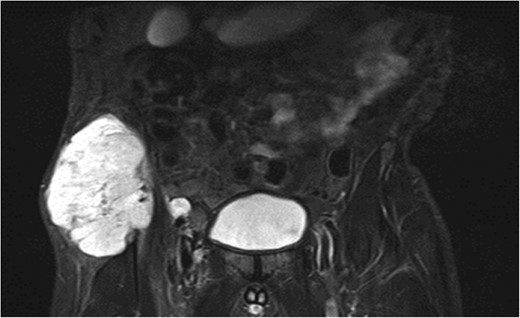

A previously fit and well 68-year-old male presented with a 6-month history of pain in the right hip. On examination this was localised to the superior area of the hip joint where a bony mass could be palpated. A pelvic radiograph was performed (Fig. 1) showing a bony exostosis on the right iliac wing. To characterise the lesion further, a pelvic Magnetic resonance imaging (MRI) scan was performed (Fig. 2). Appearances were consistent with an osteosarcoma and referral to the local sarcoma centre for histological investigation was made. Surprisingly, sampling from biopsy showed invasive well-differentiated adenocarcinoma. Staging computed tomography (CT) scanning did not reveal a primary source for the tumour but did identify thickening of the descending colon (Fig. 3) and lymphadenopathy involving the left supraclavicular, thoracic, paravertebral, retro-crurual and right inguinal regions. There was no evidence of tumour in the liver, lung or other parts of the skeleton. Subsequently, colonoscopy identified the thickened lesion as a hepatic flexure adenocarcinoma (Fig. 4). Biopsy at the time of endoscopy revealed the lesion at the hip to be a metastasis.

Intraluminal images demonstrating a lesion at the hepatic flexure.